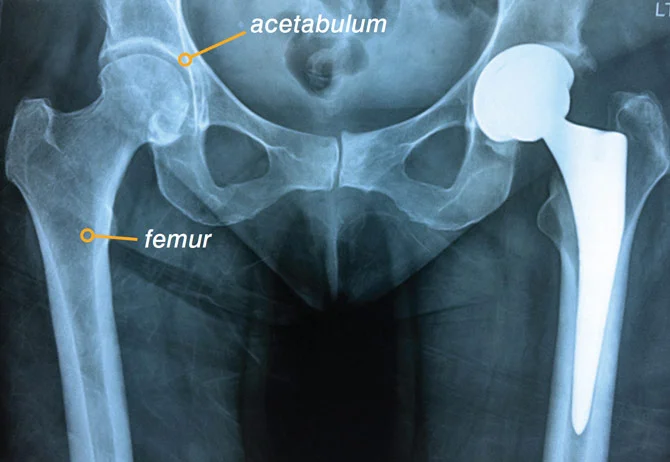

HIP REPLACEMENT SURGERY

Hip replacement surgery is designed to change the natural history of an and restore function and relieve pain. This is one of the more successful orthopaedic procedures in achieving good pain relief and restoration of function.